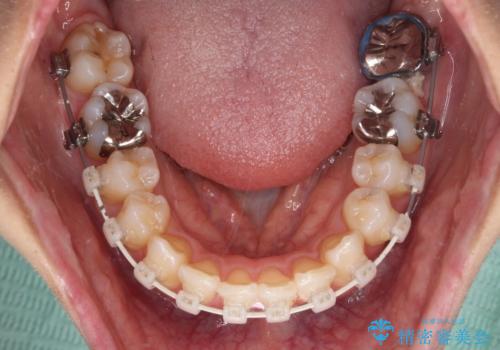

- 審美装置

- 3年7ヶ月

- 10-30回